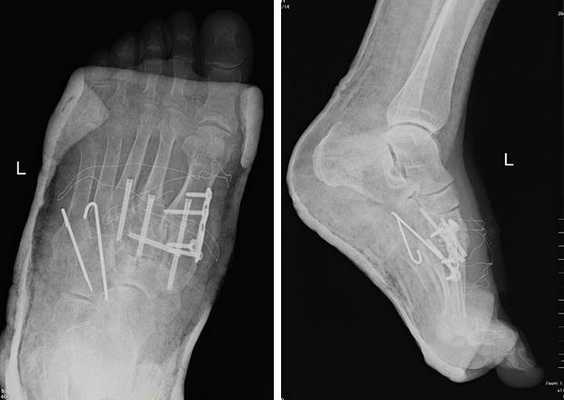

Ниже приведу пример лечения пациента с затарелым вывихом в суставе Лисфранка, которое проходило в стенах нашего отделения.

Пациенты с переломо-вывихами в суставе Лисфранка часто оказываются в ситуации, когда никто из врачей не хочет за них браться. Так случилось и с пациентом Ж. 64 лет, который получил травму ещё в 2001 году, но оперировать его отказались. Боль и деформация прогрессировали, и на протяжении последних 10 лет пациент уже не мог пройти больше 800 метров. Постоянное ношение ортопедических стелек не давало облегчения симптомов.

После осмотра в отделении ортопедии №2 ГКБ №13 принято решение о проведении операции - открытому устранению вывиха, артродезе 1-2-3 плюсне-клиновидных суставов, 1 межклиновидного сустава при помощи винтов и пластины, трансартикулярной фиксации спицами 4-5 плюсне-клиновидных суставов.

Первым этапом выполняется удаление костно-хрящевых экзостозов и рубцовых тканей из области всего сустава Лисфранка. После этого дистальный отдел стопы приобретает мобильность, достаточную для восстановления нормальной анатомии. Остатки суставного хряща полностью удаляются с 1-2-3 плюсне-клиновидных суставов, 1 межклиновидного сустава при помощи долота, осцилляторной пилы, кусачек Люэра, острой ложки Фолькмана. Для репозиции используются костные цапки.

Вершиной, ключом, блокирующим клином - в общем главной частью сустава Лисфранка является 2 плюсне-клиновидный сустав. По этой причине мы предпочитаем начинать фиксацию именно с него. Для артродеза используем винты с направленной в разные стороны резьбой FT Arthrex диаметром 4 мм. Они позволяют создать мощную межфрагментарную компрессию, а за счёт глубокой резьбы очень надёжно фиксируются в кости.

После восстановления 2 луча выполняем артродез межклиновидного сустава и 1 плюсне-клиновидного сустава. Учитывая что основная нагрузка ложится на 1 луч, дополнительно стабилизируем его при помощи пластины.

В стационаре пациент находится первые 2 суток после операции. Это необходимо для купирования болевого синдрома, и контроля послеоперационной раны. На 3 сутки пациент выписывается домой в гипсовой лонгетной повязке, на костылях. На ногу наступать нельзя до 6 недль после операции. Послеоперационные швы снимаются через 2 недели, лонгетная повязка при этом может быть заменена на циркулярный обычный или пластиковый гипс или ортез.

В итоге через 3 месяца мы получаем стабильную, безболезненную, опороспособную конечность. Через 6 месяцев можно начать спортивные нагрузки.